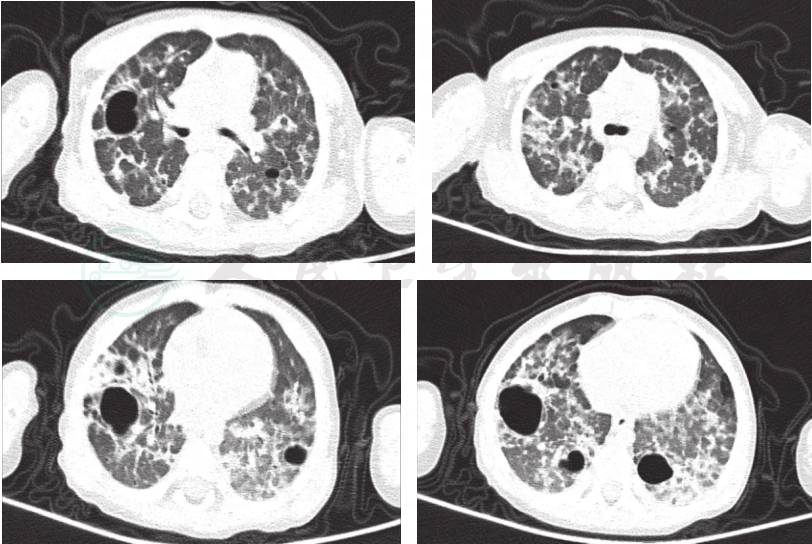

入院后做肺部HRCT,表现为双肺多发高密度斑片影,散在大小不等的囊性透光区,肺间隔增厚,肺门影不大,各层面未见肿大淋巴结(图2)。完善血常规、CRP,以及肺炎支原体、病毒抗体、结核斑点试验等均未找到病原,不支持感染性疾病诊断,嗜酸性粒细胞总数及分数正常不支持嗜酸性粒细胞性肺泡炎。RF、抗心磷脂抗体(ACA)、抗中性粒细胞胞质抗体测定(ANCA)及抗核抗体系列(ANA)均阴性,初步除外结缔组织病。根据HRCT特征性改变,高度怀疑肺朗格汉斯细胞组织细胞增生症,首先应完善肺活检,但患者出现肺部多发大泡气囊样改变,为肺活检的禁忌证。因此,完善皮肤活检以及骨髓象检查,在皮肤活检组织及骨髓象中均发现组织细胞增生(图3)。于入院4天后,转入血液科进一步诊治,建议给予长期口服小剂量激素,但家属不同意化疗,退院,院外中药(具体成分)不详。

图2 入院后肺部HRCT提示:双肺多发高密度斑片影,散在大小不等的囊性透光区,肺间隔增厚

肺朗格汉斯细胞组织细胞增生症,诊断依据:①慢性咳嗽、干咳为主,夜间咳嗽明显,活动后气促;肺部HRCT,表现为双肺多发高密度斑片影,小叶间隔增厚,双肺散在大小不等囊性透光区;②反复出现皮疹,分布在躯干部及头皮部,表现为大小不一、形状不规则红色斑丘疹,伴有少许渗出;③中枢性尿崩症,表现为多饮多尿,尿比重降低,脑垂体受累,脑垂体增强MRI显示垂体可见一弱强化灶(大小约2mm×3mm);④骨髓像显示朗格汉斯细胞。